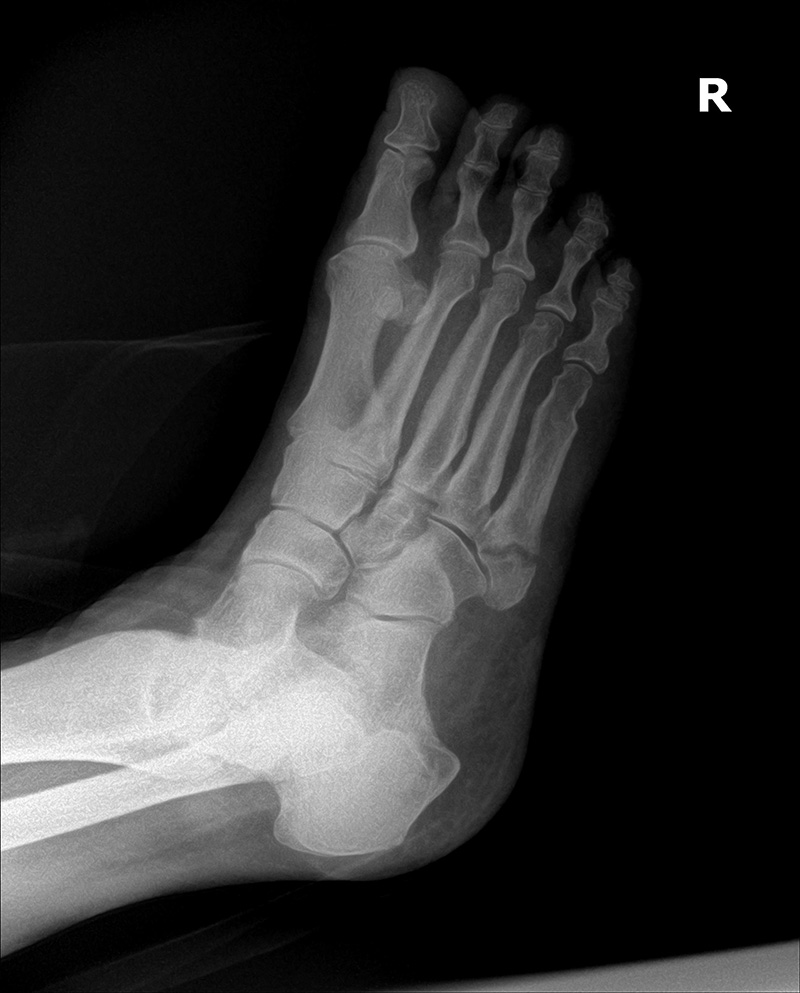

Initial Oblique view to post 4 week oblique view